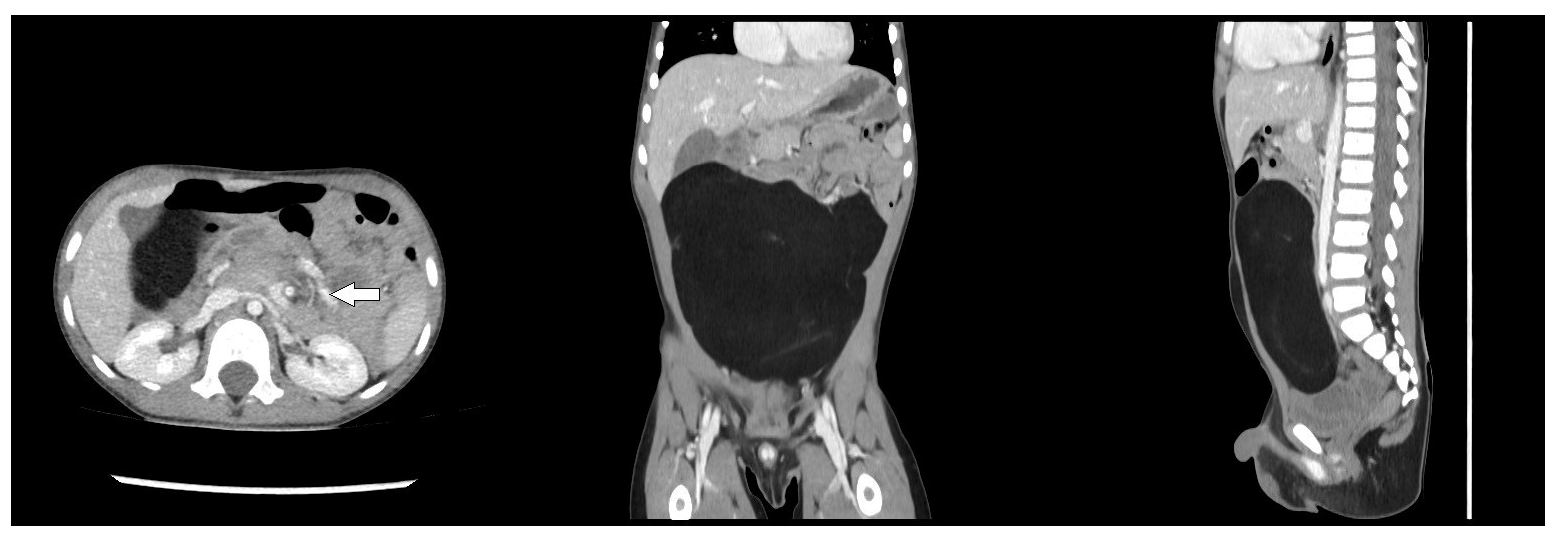

2. Case Presentation